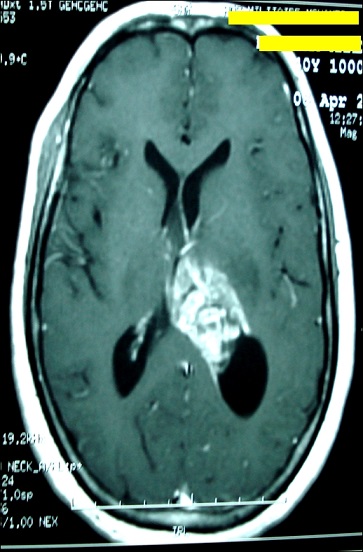

Intraventricular glioblastoma

Glioblastoma represents 15%-20% of all intracranial tumors and approximately 50 % of gliomas in adults. Although capable of arising anywhere in the central nervous system, these tumors mainly present as a frontotemporal lesion (63%) of the cerebral cortex. But, intraventricular glioblastoma is rare and only few cases have been reported in the literature. We report a case of 40-year-old woman who had a headache, vomiting and visual disturbances that persisted for four weeks. Magnetic resonance imaging showed an intraventricular lesion with inhomogeneous enhancement and infiltrative borders. These characteristics are consistent with other differential diagnoses: carcinomas, ependymomas and choroid plexus papillomas. The patient underwent a stereotactic biopsy allowed the final diagnosis of intra ventricular glioblastoma.